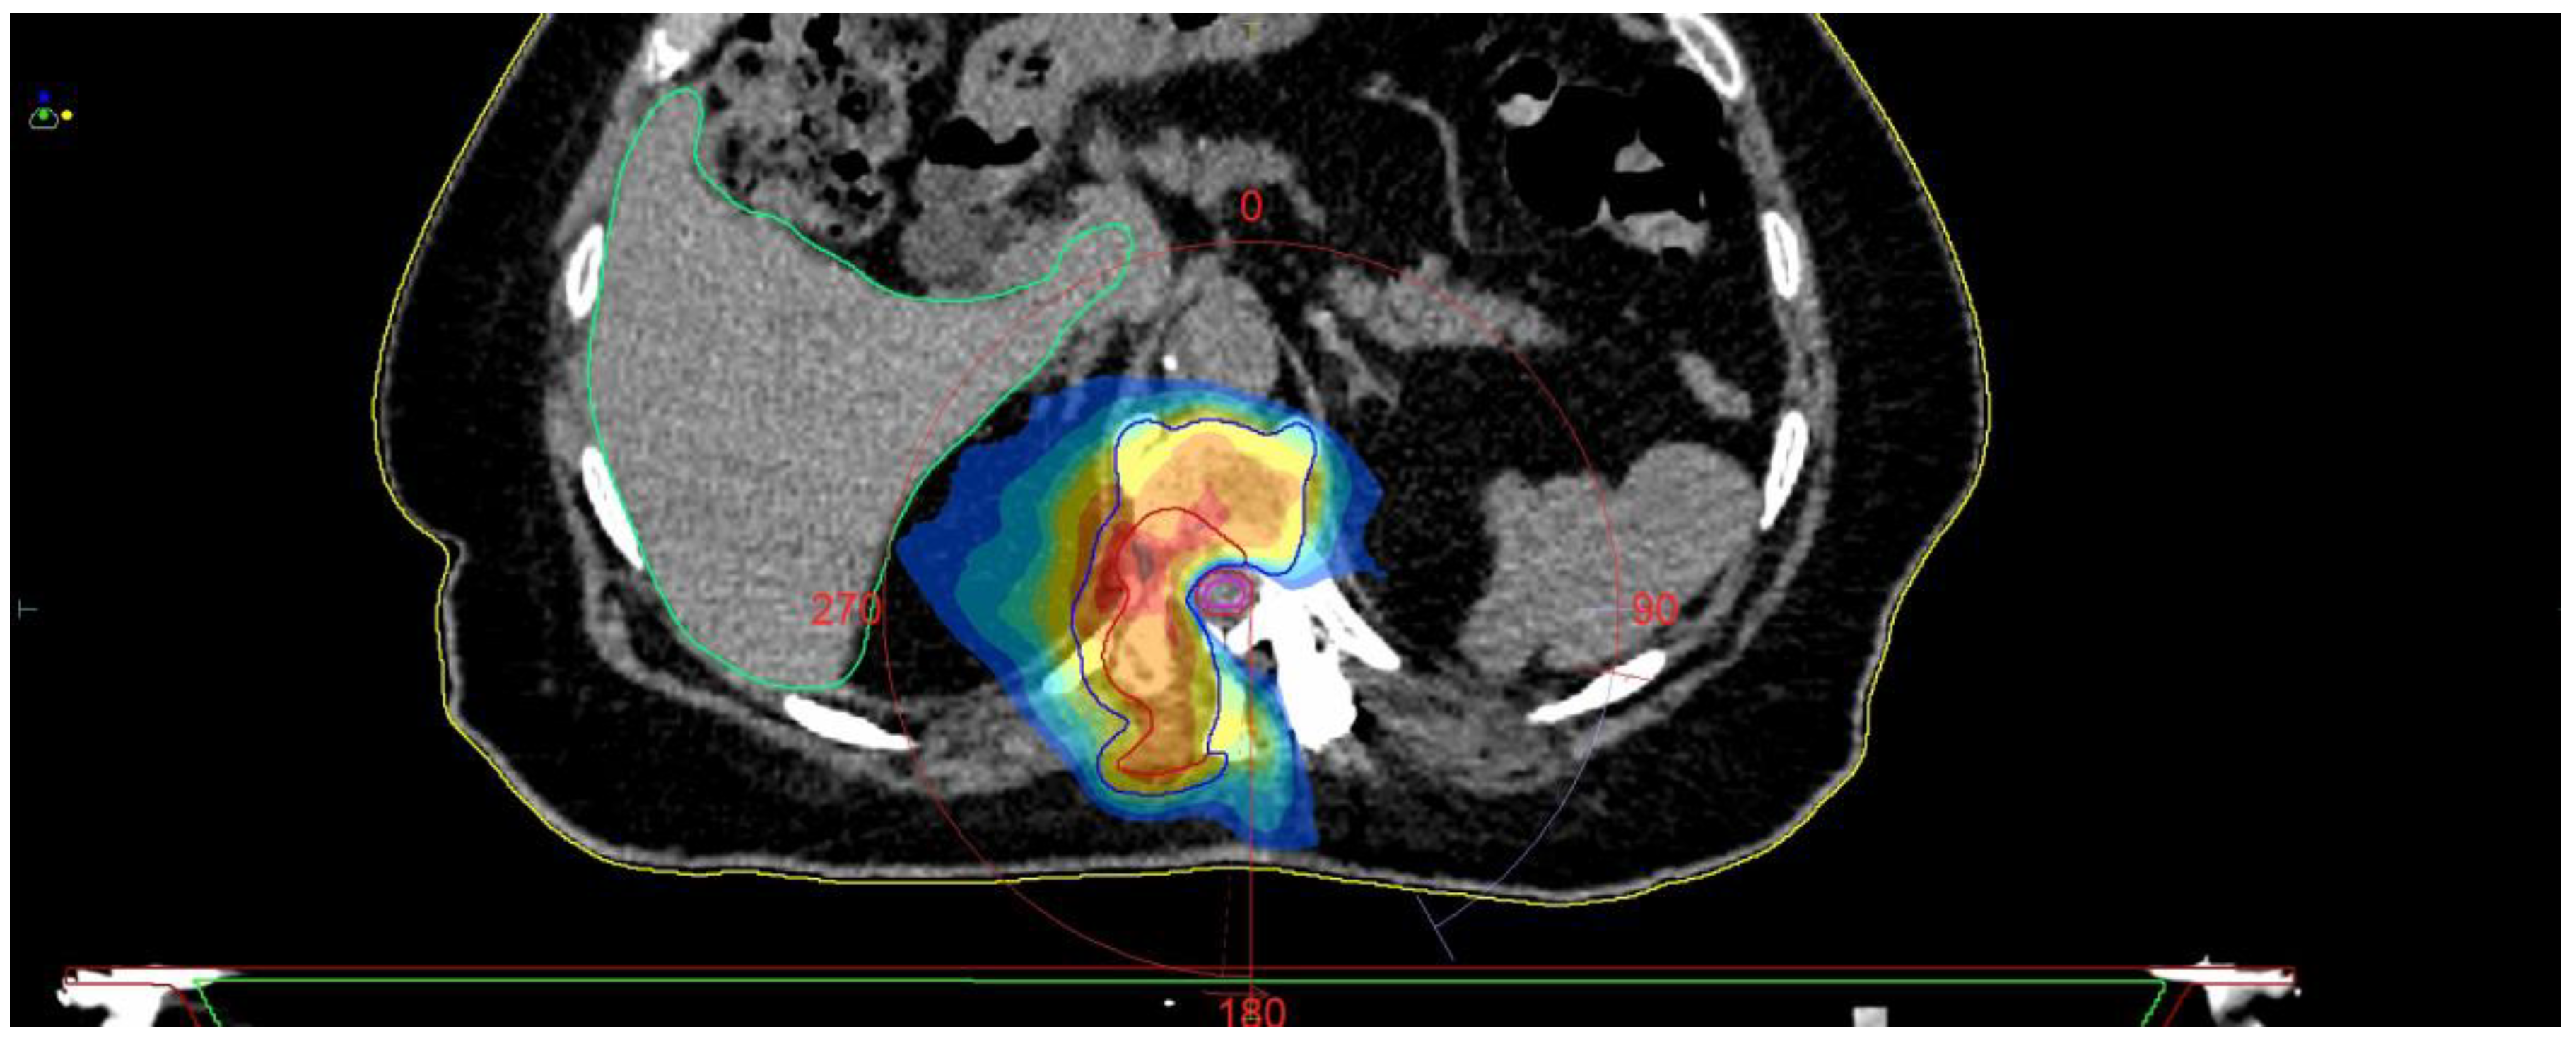

Fully Endoscopic Spine Separation Surgery in Metastatic Disease—Case Series, Technical Notes, and Preliminary Findings

2. Materials and Methods

3. Results